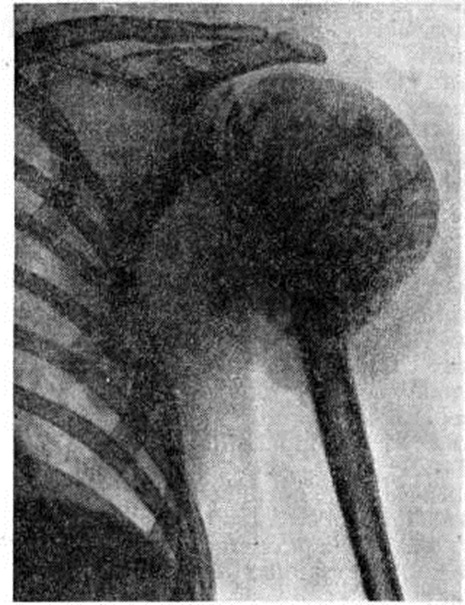

Рентгеновские снимки саркомы плечевого сустава